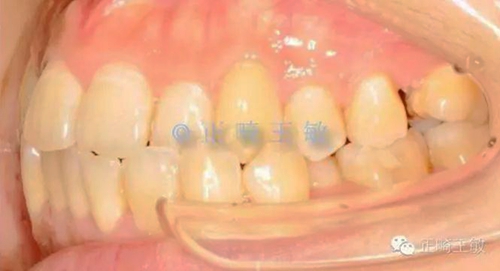

雖然這個(gè)時(shí)候正畸并沒(méi)有結(jié)束,但對(duì)于種植來(lái)說(shuō),間隙和排列,已經(jīng)足夠了,畢竟種植周期也要4個(gè)月,后面的治療就是繼續(xù)關(guān)閉間隙,調(diào)整咬合,同時(shí)等著那顆種植牙生根發(fā)芽。來(lái)看看最終的樣子:

10.jpg

一年后復(fù)查,沒(méi)有任何問(wèn)題。